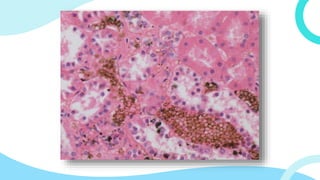

A. PIGMENTO DE FORMALINA

• Pigmento color marrón-

negro por la reacción de

la formalina con los

derivados de la

hemoglobina.